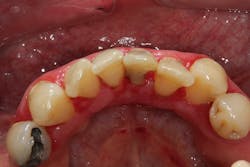

One reason people develop gummy smiles is inflammatory-induced gingival enlargement, typically caused by biofilm (bacteria) and the host response. Gum disease (gingivitis and periodontitis) can result in gum tissue swelling, redness, gum overgrowth, and bleeding (figure 1). In addition to bacterial infiltration of the gums due to poor oral hygiene, orthodontic appliances have been associated with gingival enlargement since braces can act as food traps (figure 2).Further reading: Considerations when using veneers to fabricate a perfect smile